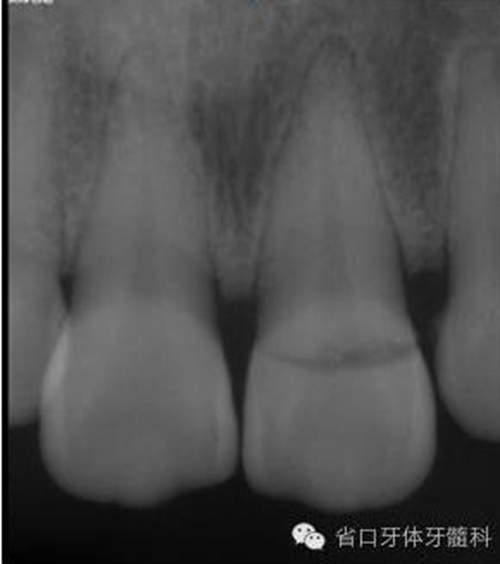

圖3. 術(shù)前X線片